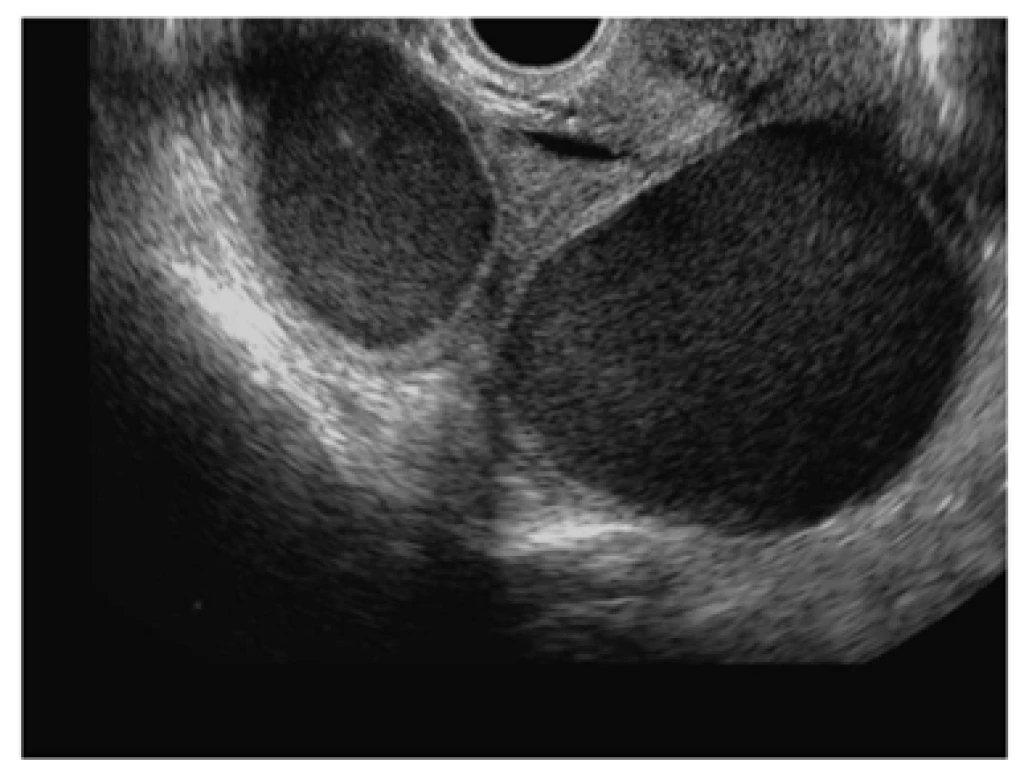

Kissing ovaries

Echobeeld "kissing ovaries": beide ovaria bevatten typische endometriosecysten met matglas aspect, aan elkaar gefixeerd door adhesies in de holte van Douglas.